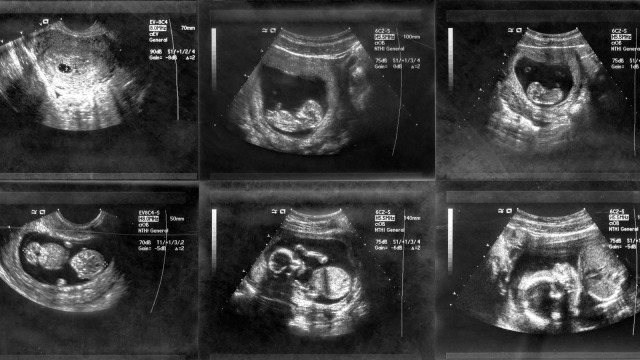

Tahap Perkembangan Janin pada Trimester Pertama

Sebelum janin berkembang sebesar ukuran bayi baru lahir, tahapan tumbuh kembang janin dimulai terlebih dulu dari embrio.

Setelah itu, embrio akan berkembang menjadi janin, kemudian janin mengalami perkembangan secara bertahap pada tiap trimesternya. Berikut perkembangan janin pada tiga bulan pertama kehamilan seperti yang dikutip kumparanMom (kumparan.com) dari WEBMD.